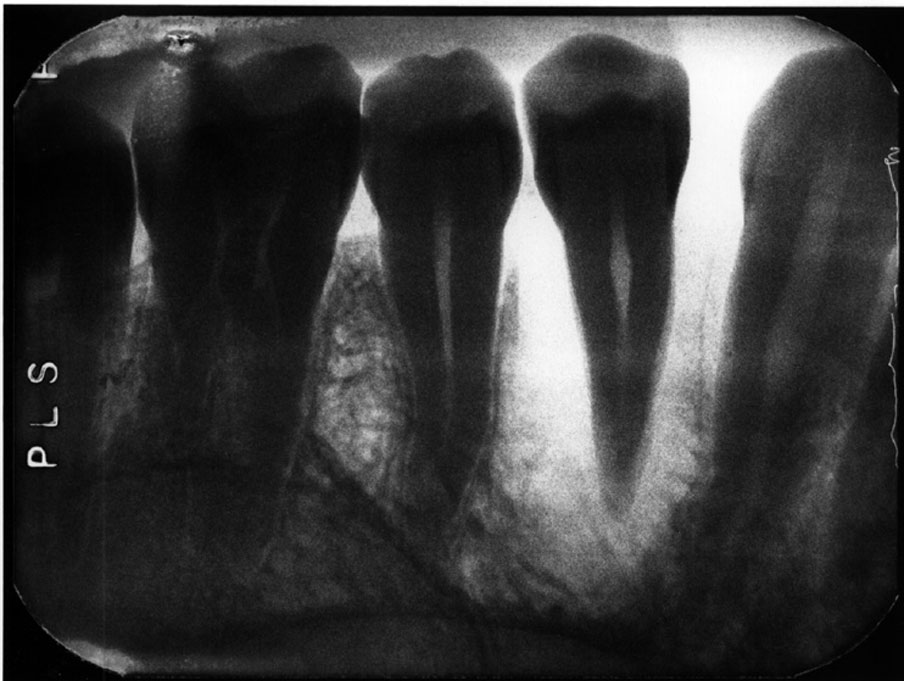

Processing Errors In Dental Radiography Digital . Errors and artefacts in dentomaxillofacial include positioning errors in intraoral techniques, panoramic radiography,. Using digital imaging leads to the elimination of processing errors making the technician or dentist to focus on the positioning errors to ensure. Chemical contamination errors include developer spots which is when the developer comes in contact with film before processing. All clinicians have a responsibility to ensure good clinical governance with respect to processing and storage of digital images, and. Identify and describe the appearance of the following exposure errors:. Define the key terms associated with exposure and technique errors. In this article we hope to inform you how you can minimize patient and operator exposure identify and proper errors in digital intraoral.